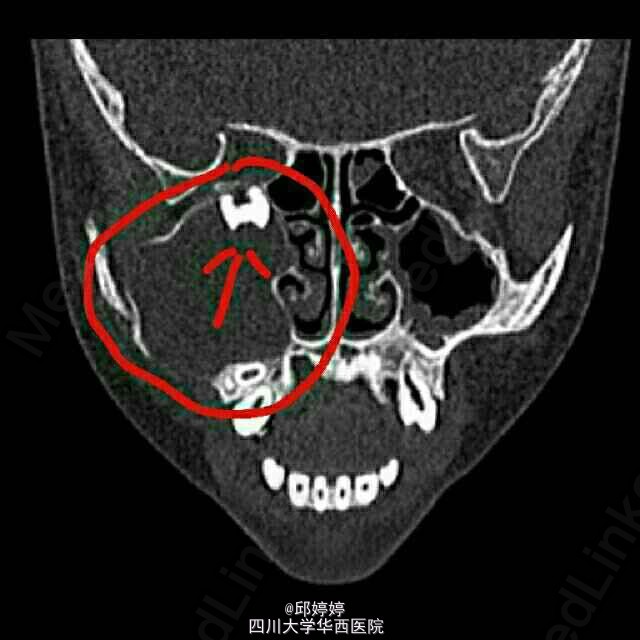

上颌窦牙源性角化囊肿

患者,女,15岁。右侧面部水肿。

CT如图1

该病变经手术成功切除,病理检查证实为牙源性角化囊肿。

该囊肿类型少见,囊肿生长于上颌窦,内含有两颗高密度的牙齿,这两颗牙齿还成为了右眼眶下壁的一部分。